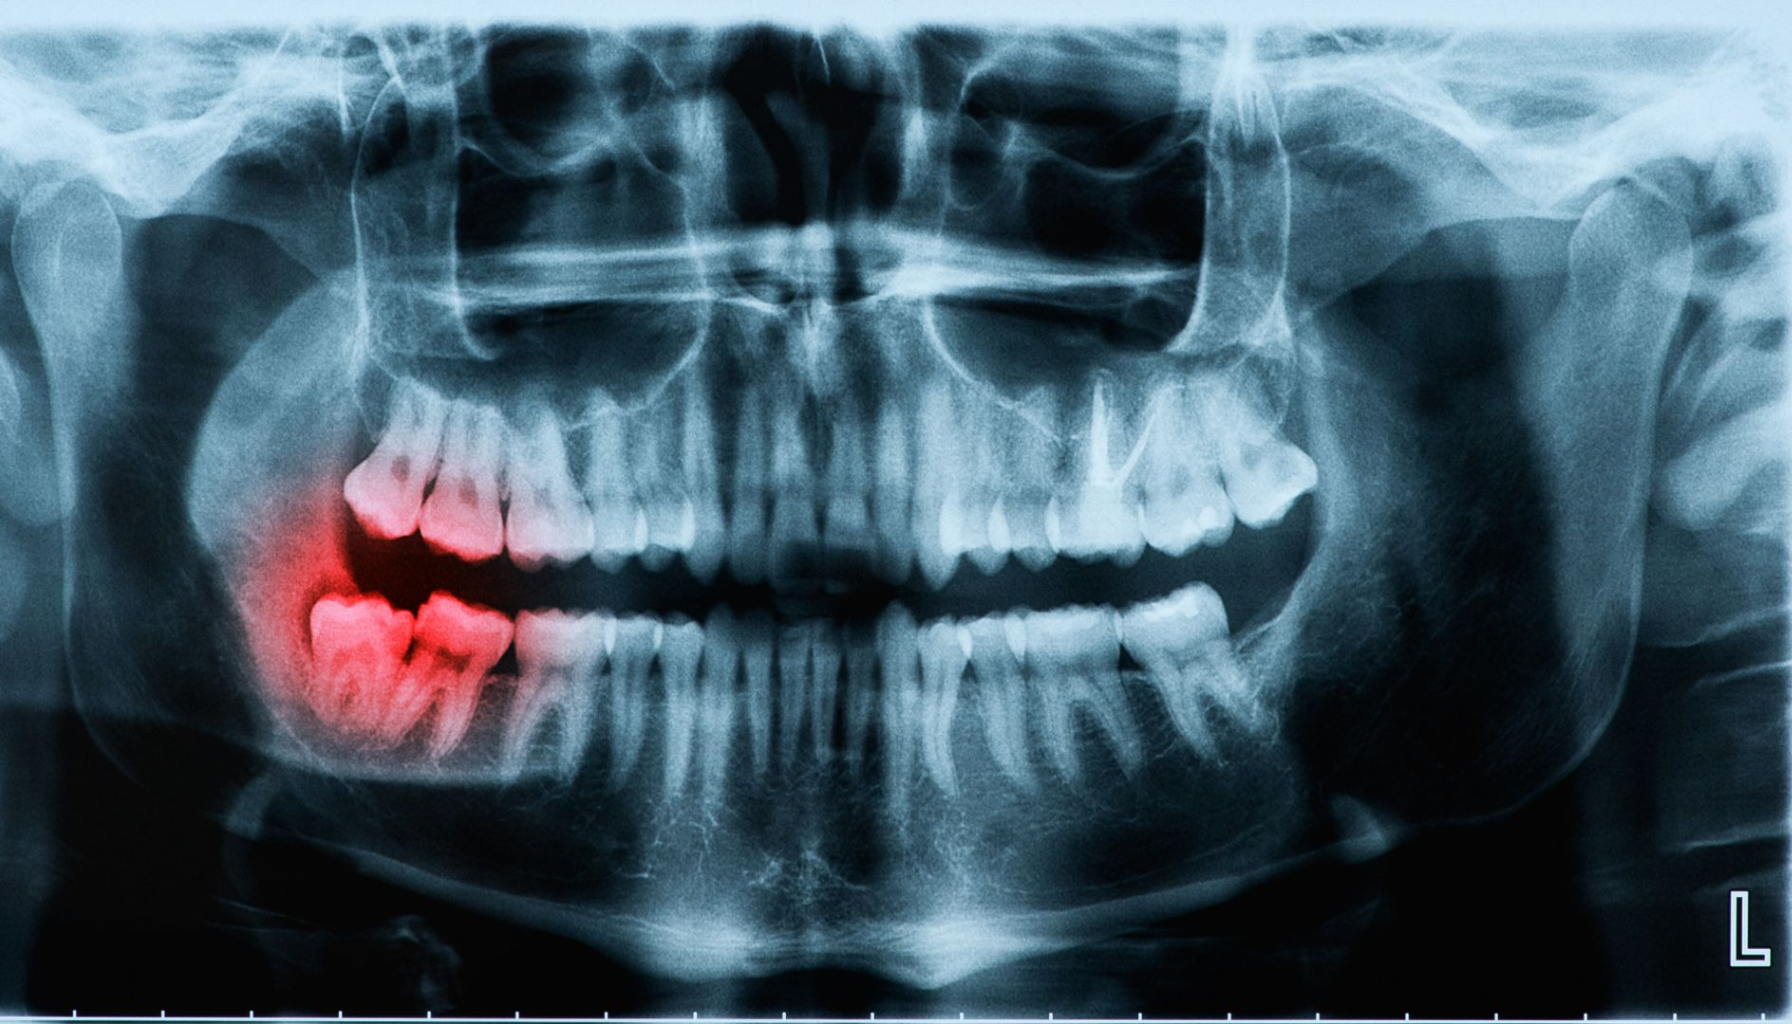

Perikoronitt er en betennelse som oppstår rundt delvis frembrutte visdomstenner.

Perikoronitt er en betennelse i vevet som omgir en visdomstann som ikke har kommet helt frem. Når tannen delvis bryter gjennom tannkjøttet, skapes det en liten lomme der bakterier lett kan samle seg. Denne lommen er vanskelig å holde ren, og resultatet kan bli infeksjon og betennelse.

Kort forklart: perikoronitt er en lokal tannkjøttsinfeksjon som oppstår fordi visdomstannen ikke får nok plass til å bryte frem, og dermed skaper et miljø hvor bakterier trives.